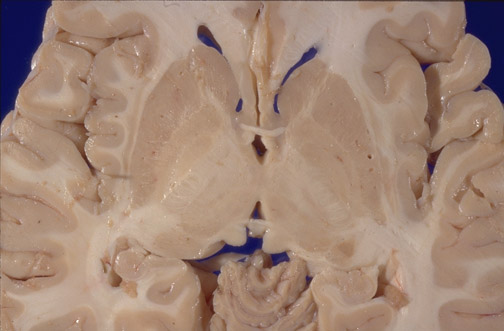

Identify the following regions of the brain on transverse section in the image above: Anterior Commissure - Posterior Commissure - Head of Caudate - Putamen - Globus Pallidus - Internal Capsule - Thalamus - Habenula - Hippocampus - Cerebellum